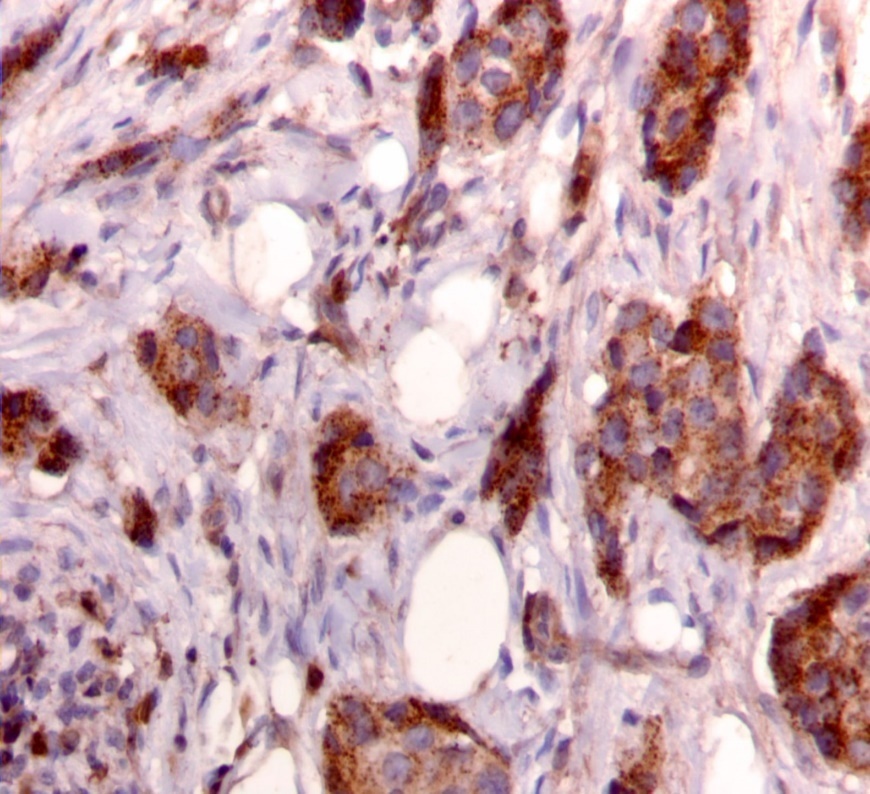

Figure 1.Nuclear staining pattern for IRS-1. (IRS-1 immunohistochemical stain, 200x magnification)

Nuclear staining pattern for IRS-1. (IRS-1 immunohistochemical stain, 200x magnification)

We used the following histologic criteria for IRS-1 and IRS-2 staining patterns which are outlined in a previous study.13 For IRS-1, a nuclear pattern was defined as diffuse nuclear staining (Figure 1). IRS-2 staining patterns were defined using the following criteria: Diffuse cytoplasmic staining was defined as evenly distributed cytoplasmic reactivity (Figure 2); punctate cytoplasmic staining was defined as clearly demarcated puncta of staining within the cytoplasm (Figure 3); and membrane staining was defined as focal or diffuse membranous staining (Figure 4). Sections of normal pancreas and normal breast tissue were used for positive and negative controls. The pathologists assessing staining patterns were blinded to the tumor recurrence score and all other data at the time of assessment.